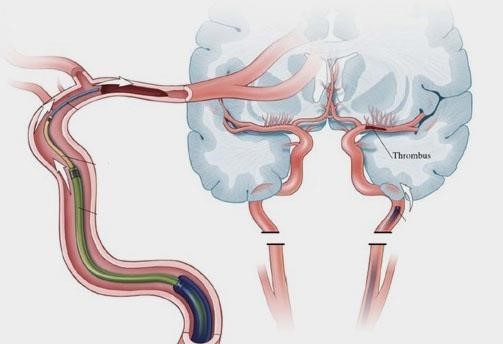

Thrombectomy is an emergency procedure performed by a specialist team led by a doctor called an Interventional Neuroradiologist.

The doctor uses specialised equipment and guidewires to physically remove the clot from the artery in the brain in order to restore the blood supply. If mechanical thrombectomy is not feasible, there is no known better alternative treatment to remove or dissolve the clot. If untreated, the patient’s stroke symptoms can get worse.

- An incision into the femoral artery in the groin is made and a thin plastic tube (guidewire) is inserted.

- An X-ray detectable contrast dye is injected to better visualise the blood vessels which supply up to and into the brain.

- An X-ray scanner then monitors the highlighted blood vessels and helps guide the route of the catheter up to the brain, and towards the artery which is blocked by the blood clot.

- Once the blockage is reached, a clot-removal device is placed through the catheter tube to take the clot out. A special equipment such as a small wire mesh (stent retriever) or suction devices is used to remove the blood clot and restart blood flow to the affected part of the brain.